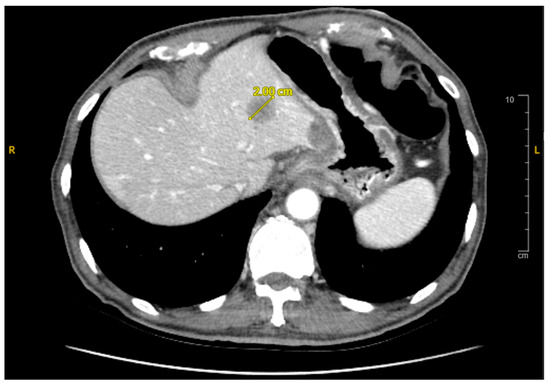

2. Case Presentation